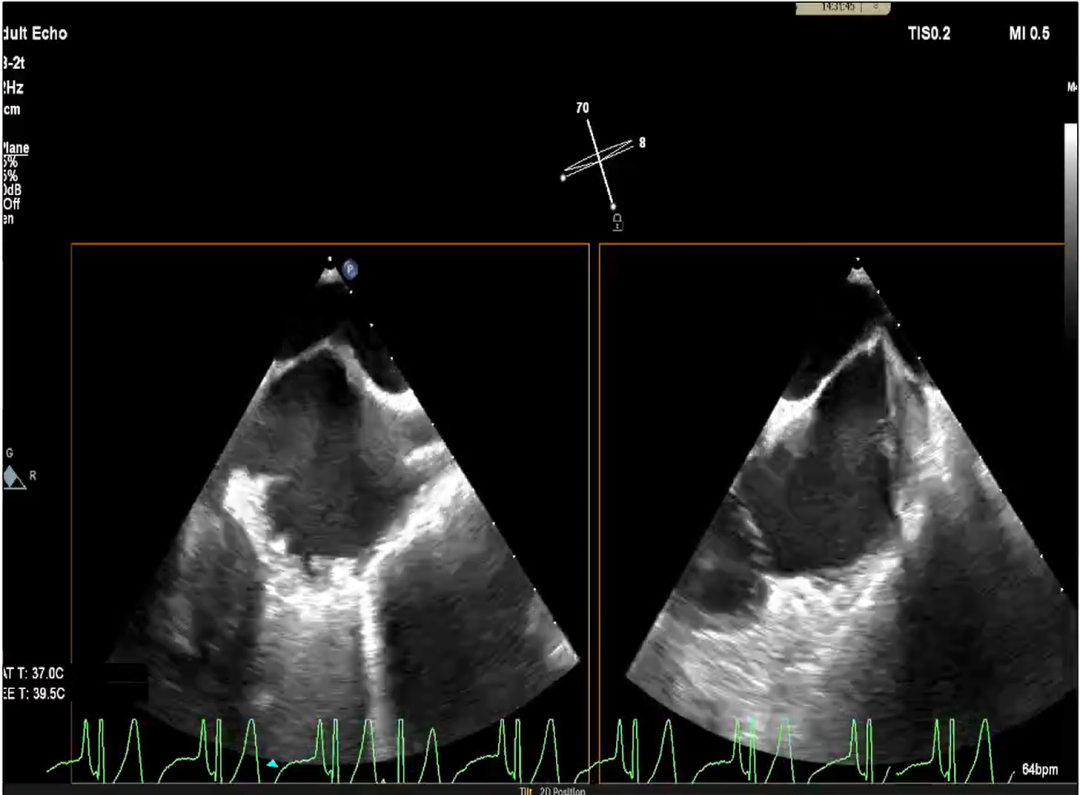

术前X-plane

术前X-plane Color

术前X-plane

术前X-plane Color

术前X-plane

术前超声 Color

术前X-plane

术前X-plane Color